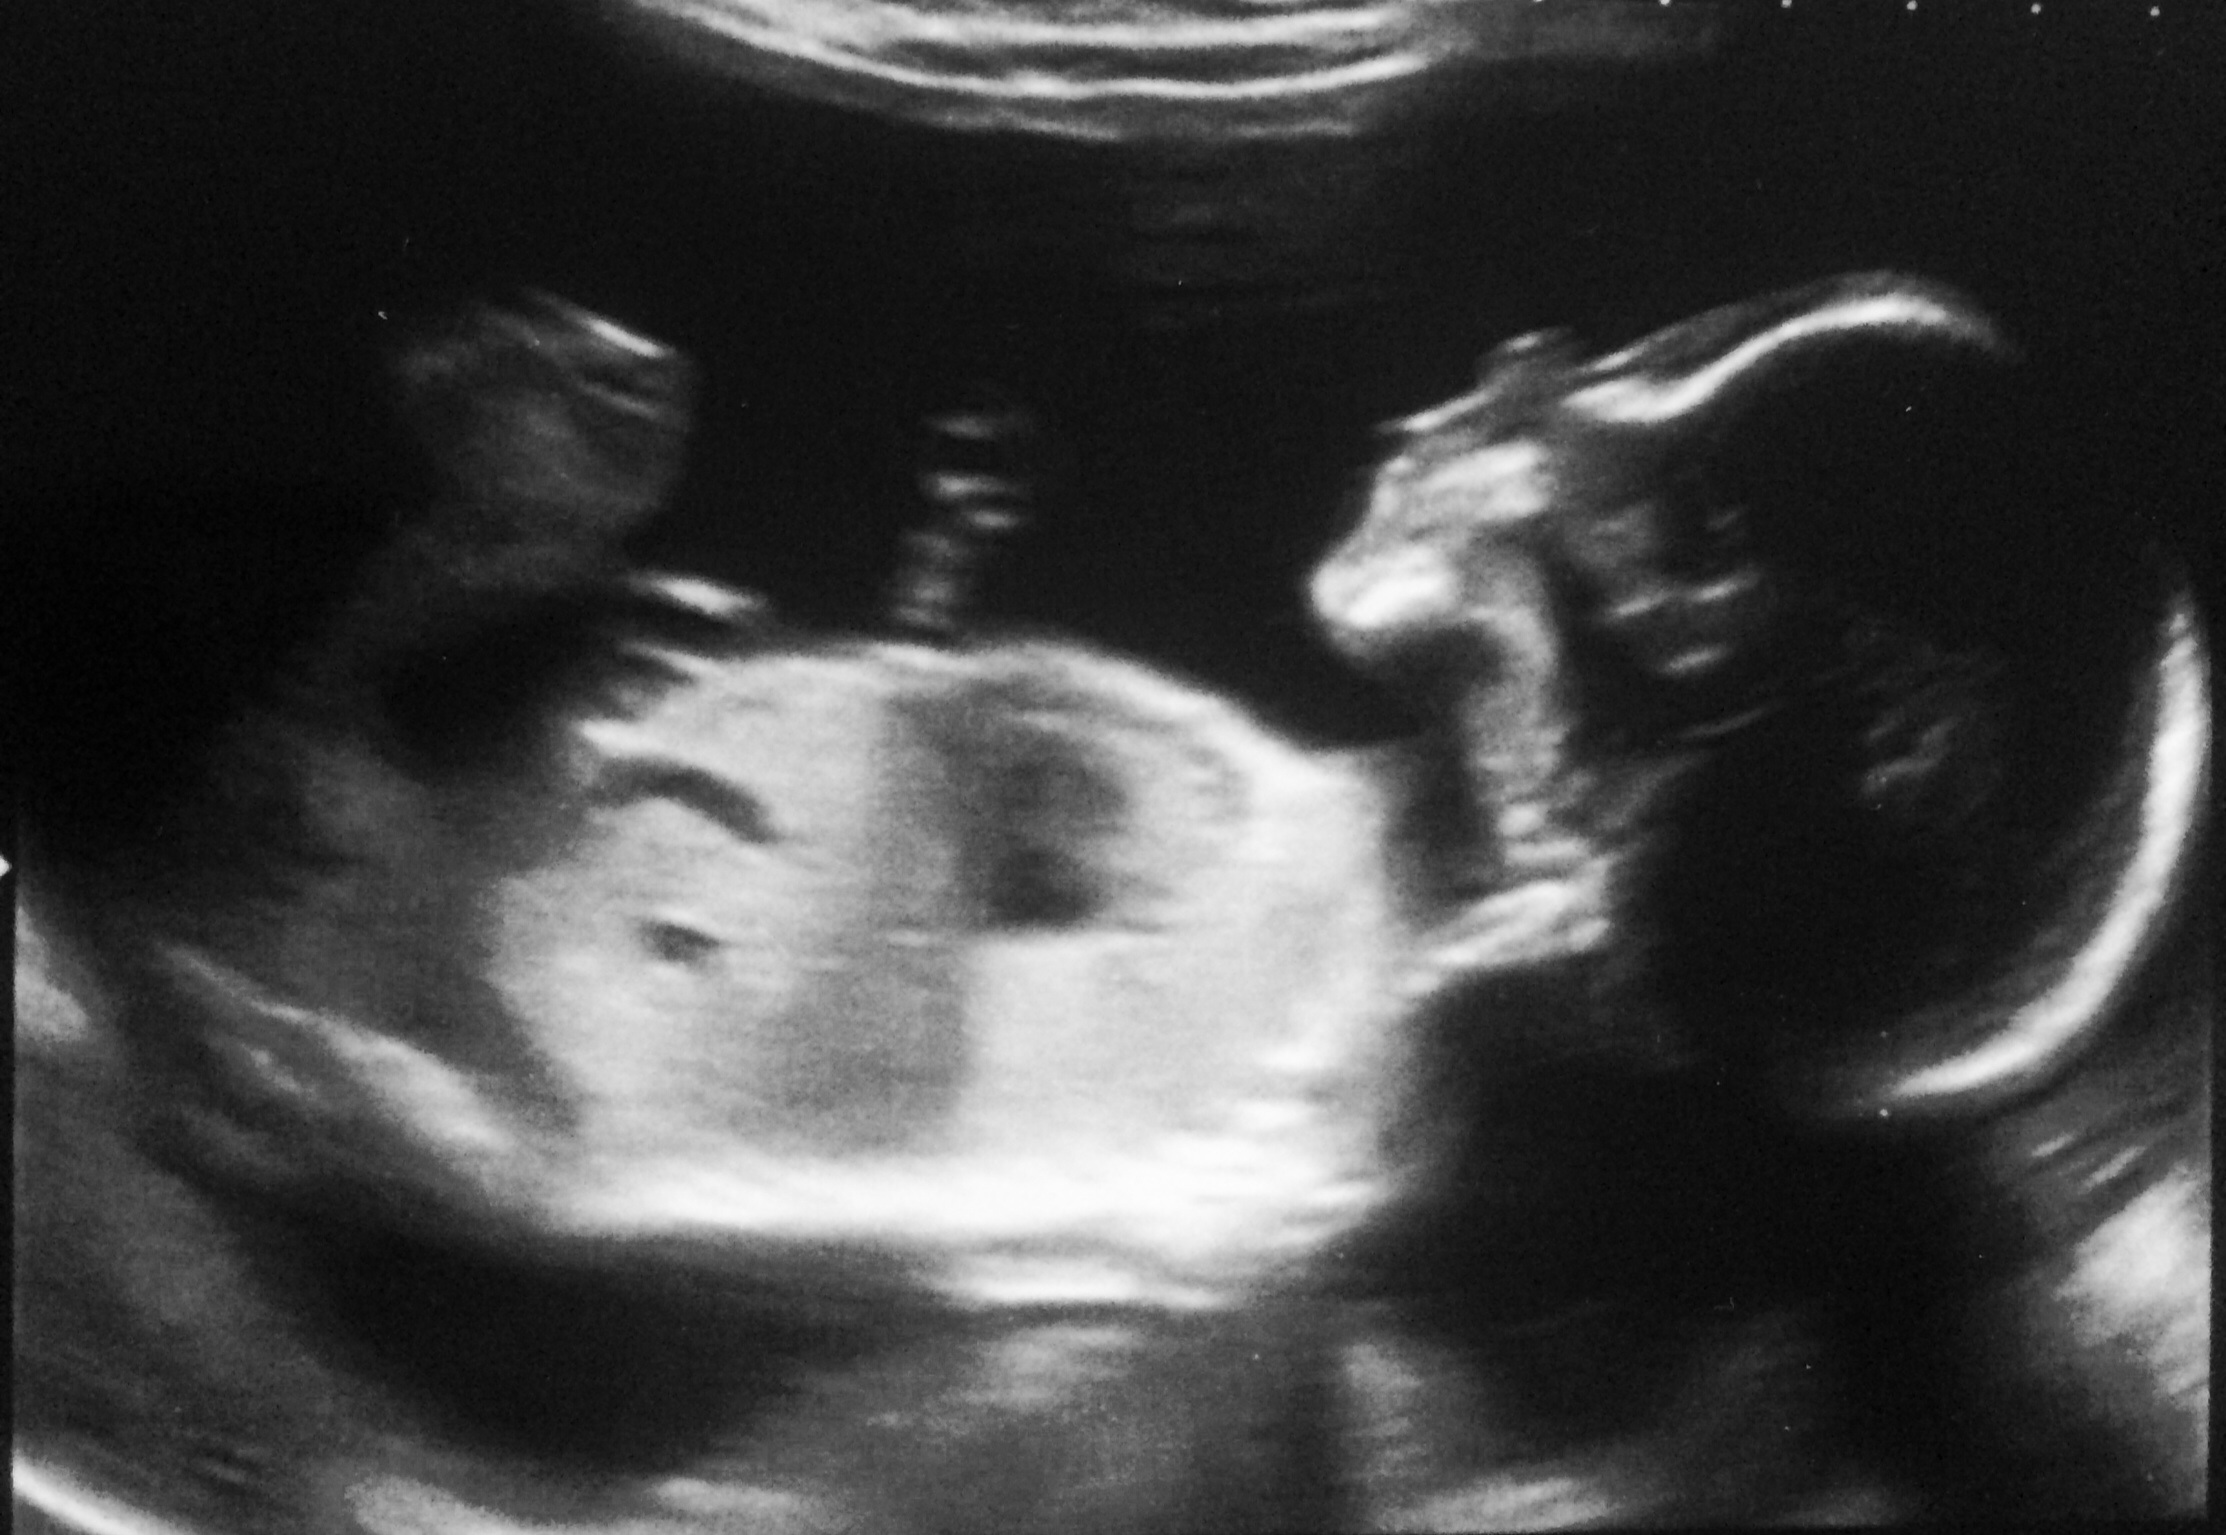

Just went for u/s today. Baby is doing great and measuring correctly for his dates. Everything looked fab. DH is thrilled to soon being a daddy for the first time!

Got to spy on the little pickle while he bobbed about inside me. Was so nice to see baby again and now I get to call him He. Strange to think that next time I see him he will be here in the outside world!

He is most definitely a boy as I saw the evidence. Baby wasn't shy. Another exhibitionist male.